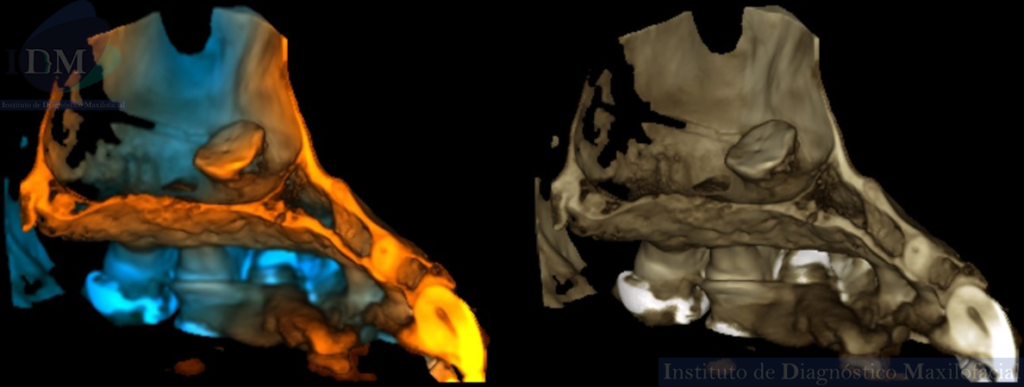

A la evaluación de la tomografía computarizada de haz cónico (TCHC) en los cortes axiales, transaxiales y en la reconstrucción 3D se observa una estructura ovalada hiperdensa heterogénea con contenidos mixtos irregulares localizada en piso del seno maxilar izquierdo con extensión hacia el antro sinusal. Además, en las imágenes tangenciales se observa la presencia de un antrolito adyacente a nivel de la pieza 26.

RECONSTRUCCIÓN 3D